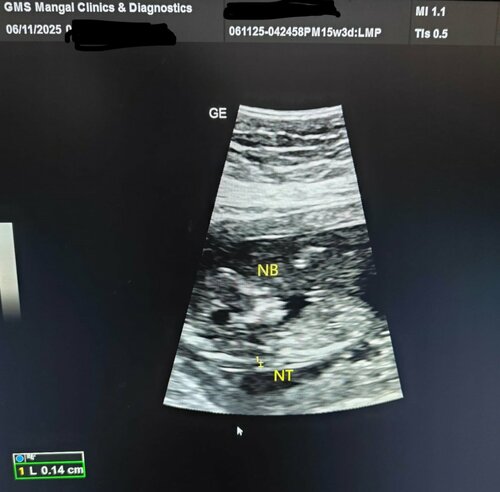

NT & NB Prenatal Screening Expert | Dr. Deepti Agarwal

Dr. Deepti Agarwal, an Expert Consultant Radiologist at GMS Mangal Clinic and Diagnostics, Dehradun, emphasizes the importance of the NT & NB scan...